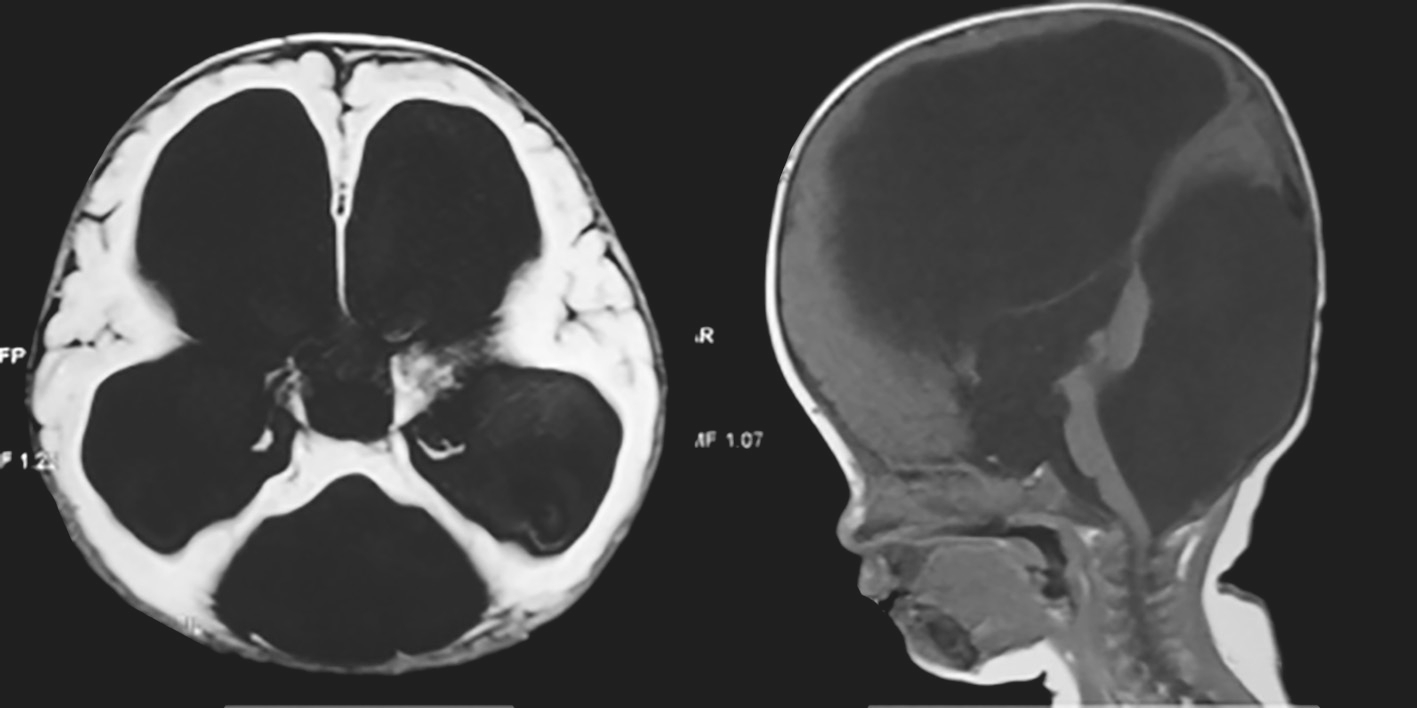

3.辅助检查 头颅CT示枕骨局部缺损,枕部脑膜膨出。头颅MRI示枕部脑膜膨出(图4-1-1)。

图4-1-1 头颅MRI示枕部脑膜膨出

辅助检查:头颅MRI(图4-1-4)检查示双侧脑室系统对称性显著扩大,脑室前、后角变钝,双侧大脑半球脑实质明显变薄,脑实质内未见明确异常信号,颅后窝枕大池扩大,双侧小脑半球受压、上抬,小脑幕抬高,小脑蚓部缺如。

图4-1-4 头颅MRI检查